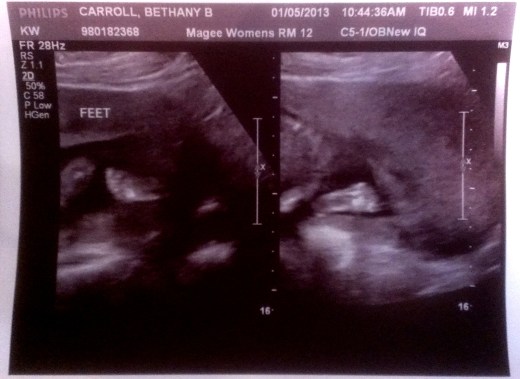

It’s a girl!

Well, that’s what they told us.  Words can’t express how beautiful this is to me.  Seeing that little heart beat today made it all hit me.

I’m sure I’ll post more funny goofy silliness about having a daughter eventually, but right now I’m just so happy and I wanted to share.  I can’t wait to meet her!

Also, the feet on the printout were adorable, but I could be biased: